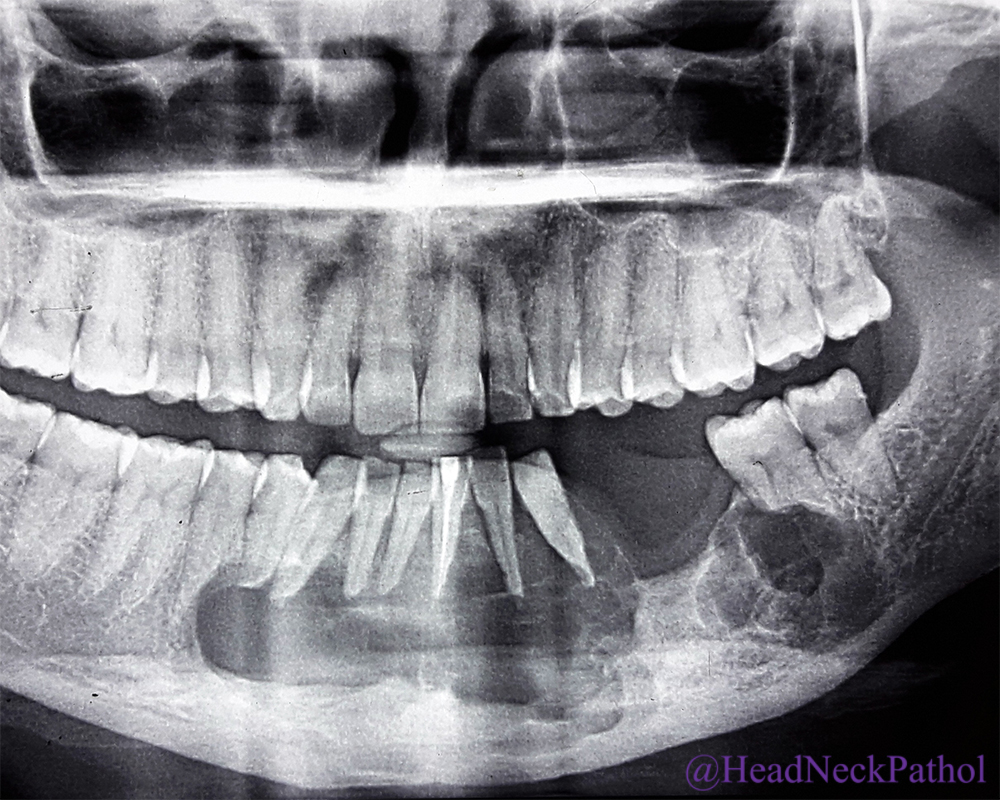

radiographic features that could help in diagnosing ameloblastomas include its. As they usually do not form metastasis, they are. ameloblastoma (ab) is an aggressive benign odontogenic neoplasm arising from epithelial remnants of the. ameloblastoma are the most common odontogenic tumor. ameloblastomas originate within bone, apart from the peripheral subtype which arise in the gingiva or. ameloblastomas are rare, odontogenic tumors.